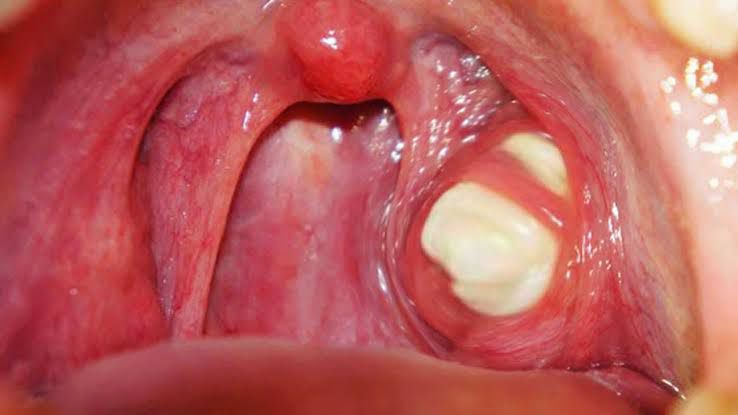

Some tonsil stones don’t cause any symptoms. If you do have symptoms, they may include: Bad breath (halitosis). Cough. Earache. Sore throat. Bad taste in your mouth. Small white or yellow stones that you may spit up. Other symptoms include: Difficulty swallowing. Feeling that something’s stuck in your throat. Small white patches on your tonsils. Throat infections that are hard to treat with antibiotics.